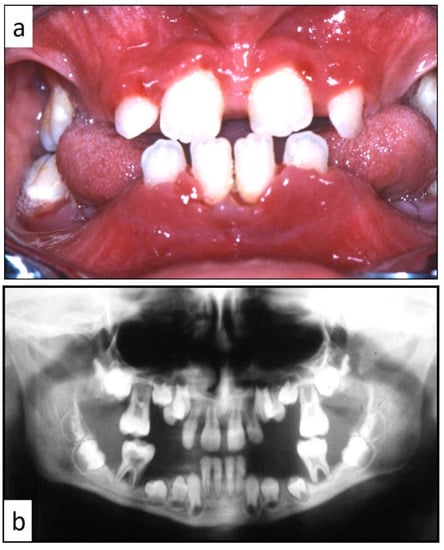

Nine patients were affected by single eosinophilic granuloma of the mandible and two of the maxilla (0–10 A; 10–18 C). Inflamed, hyperplastic, painful and often ulcerated gingival lesions were common findings in 22 cases (0–10 A; 10–18 B) (Figure 1). They were associated with deciduous teeth mobility and/or dislocation with gingival probing and periodontal bone loss in 18 cases, and to premature teeth loss with dislocation of the permanent teeth follicles and bone lesions (single or multiple) in nine cases (0–10 B; 10–18 A) (Figure 2a–d). Focal gingival swelling (often with superficial ulceration) occurred in patients with single lesion of the jaws (five in the maxilla and three in the mandible), all appearing as radiolucency with well-defined borders but, however, with rapid bone erosion (0–10 A; 10–18 C). Single lesions of the palatal mucosa were detected as the first sign in six patients (0–10 A; 10–18 B), generally appearing as reddish or strawberry gingivitis with periodontal involvement and/or complete diffusion to the palate (0–10 C; 10–18 B) (Figure 3a,b). Nine patients showed diffuse lesion of the mandible with a progressive resorption of the alveolar bone with the characteristic “floating teeth” appearance (0–10 B; 10–18 A); in six cases, localized lesions of the maxilla were synchronously detectable (0–10 C; 10–18 B) (Figure 4a,b). In addition, patients with periodontal involvement had in common a delayed diagnosis of several months as they received treatments for gingival/periodontal diseases but were unresponsive to each one. The resorption of dental roots has never been observed on either deciduous or permanent teeth. Paresthesia, due to compression of the inferior alveolar nerve, was observed in only three cases, while in six instances a pathological fracture of the mandible occurred (0–10 A; 10–18 C) (Figure 5a–c), both resulting in expansion of an osteolytic lesion. Submental, submandibular and lateral-cervical lymph nodes involvement was associated with oral lesions in 12 cases (0–10 B; 10–18 B). Adjunctive radiological examination revealed lesions of the skull in 14 patients and, respectively, two of the parietal bone (Figure 6a), two of the temporal bone, one of the zygomatic bone, and three of the orbit (0–10 B; 10–18 C). Otitis (media or externa) was referred or detected in four instances, cutaneous rush in nine (0–10 B; 10–18 C) (Figure 6b), exophthalmia in two (Figure 7a,b), while data about the contextual presence or subsequent onset of insipidus diabetes were available only in eight cases (0–10 B; 10–18 C).

Figure 1. Hyperplastic, reddish and inflamed gingiva unresponsive to conventional medical and instrumental periodontal treatments; such findings, along with the lack of multiple teeth, should arouse the suspicion of LCH in children.

Figure 4. (a,b): Involvement of the entire periodontium, gingiva (a) and alveolar bone (b), of the mandible and maxilla causing premature loss of deciduous teeth; impressive bone resorption and following difficulties in permanent teeth development; the patient was a 11-year-old male, receiving treatment for gingival inflammation and teeth mobility for several months, thus causing a delayed diagnosis of LCH.